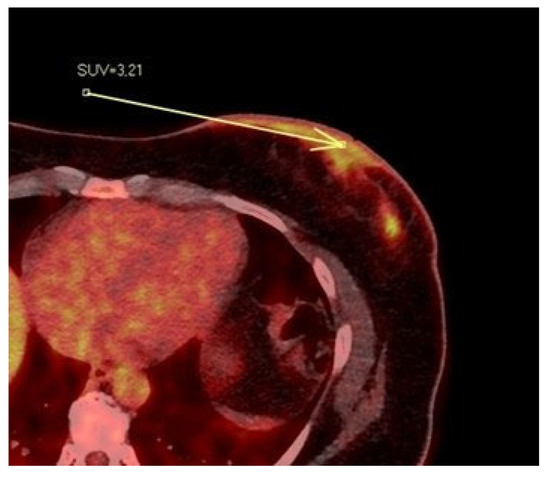

Figure 6.

Patient’s name R.M. During PET/CT, the pathological NAC-SUV value is measured at the base of the left nipple.

3.2. PET/CT Results: NAC-SUV Ratio

In our population, 33 women underwent PET/CT before starting neoadjuvant chemotherapy to assess skeletal status. For each patient, we quantitatively measured the NAC-SUV values in the malignant breast and the contralateral normal breast (Figure 6) in early-stage images (obtained one hour after radioisotope administration), delineating a three-dimensional volume of interest (VOI) over the NAC. The most representative image was selected, and the VOIs were carefully drawn to avoid including adjacent lesion areas, with the exception of the nipple presumed to be infiltrated based on imaging. We calculated the NAC-SUV ratio (R) by considering the ratio of NAC-SUV in the malignant breast to NAC-SUV in the contralateral normal breast. The NAC-SUV R was calculated only for early-stage images. The calculated mean SUV of pathological NACs was 3.59, while the mean SUV of contralateral normal NACs was 2.12. The calculated mean NAC-SUV ratio was 1.7.

Tumor invasion of the nipple is crucial to determine whether the NAC can be preserved; breast MRI is considered the most useful and accurate imaging modality for predicting nipple involvement in patients, to decide whether NSM is safe or not [13,22,23,24,25,26]. Several studies have evaluated nipple–areola complex (NAC) involvement on MRI, based on clinical and pathological features [2,4,8,14]. To our knowledge, some scientific investigations have also been conducted on the efficacy of 18F-fluorodeoxyglucose (FDG) positron emission tomography/computed tomography (PET/CT) for detecting tumor-associated NAC involvement [27,28,29,30,31]. Since nipple symptoms (e.g., nipple erosion, discharge, retraction, and cystic duct dilation) are highly suspicious for NAC invasion, there is a higher possibility of NAC involvement in patients suffering from clinical nipple changes compared to asymptomatic ones. In 2018, Yoo et al. examined 90 patients with invasive breast cancer to demonstrate the predictive value of preoperative prone 18F-FDG PET/CT for determining NAC involvement, by comparing image parameters and clinicopathological factors based on the presence and/or absence of nipple symptoms [27]. SUVmax values for NAC were obtained in the malignant breast and the contralateral normal breast. They calculated the NAC-SUV ratio using the following formula: NAC-SUVratio = SUVmax of NAC in the malignant breast/SUVmax of NAC in the contralateral normal breast. The NAC-SUV ratio was calculated for early (NAC-SUVRearly; one hour after radioisotope administration) and delayed (NAC-SUVRdelay; two hours after radioisotope administration) imaging. Seventeen patients confirmed pathological NAC involvement based on histological findings. After the multivariate analysis, NAC symptoms (p = 0.009), tumor multiplicity (p = 0.006), NAC-SUVRdelay delay (>1.23, p = 0.007), and tumor-NAC distance based on MRI (≤22.0 mm, p = 0.003) were found to be independent predictors of NAC involvement. The NAC-SUVRearly PET parameter (p = 0.018) showed predictive significance for NAC involvement in the univariate analysis but did not maintain significance after the logistic regression analysis. The authors concluded that delayed 18F-FDG PET/CT is a useful modality for predicting NAC involvement in breast cancer patients, regardless of the presence or absence of NAC symptoms and that delayed PET/CT could be performed to evaluate malignant NAC involvement during the preoperative workup [27].

Although pathological involvement of the NAC cannot always be assessed in the surgical specimen, MRI and PET/CT with SUV measurement can provide valuable information on the tumor-infiltrated nipple. In our population, the mean SUV value of pathological NAC was 3.59, while the mean SUV value of contralateral normal NAC was 2.12. The mean NAC-SUV ratio was 1.7, meaning that pathological NAC has the highest SUV value, approximately one and a half times higher than normal. In our analysis, the mean early NAC-SUV ratio (1.7) measured in early-stage findings is quite close to the late NAC-SUV ratio (1.23) calculated by Yoo et al. [27] in late-stage findings. In our case series study, among the quantitative parameters derived from PET/CT, the early-stage SUV ratio of pathological NAC compared with the contralateral normal breast offers some interesting contribution to determining the involvement of pathological NAC. The early NAC-SUV ratio (1.7) measured by us in early-stage findings (one hour after radioisotope administration) and the late NAC-SUV ratio (1.23) calculated by Yoo et al. [27] in late-stage findings (two hours after radioisotope administration) both represent the level of uptake of radioactive glucose (18F-FDG) by the pathological nipple, albeit at distinct moments of the PET examination. The two parameters appear similar, although not perfectly identical; in the work by Yoo et al. [27], the NAC-SUV ratio was calculated on delayed PET images. However, we believe that the NAC-SUV ratio calculated in our population is informative as to whether PET-CT can provide information on nipple infiltration in breast cancer, considering that the SUV of the infiltrated nipple is on average 1.7 times higher than that of the contralateral healthy nipple.